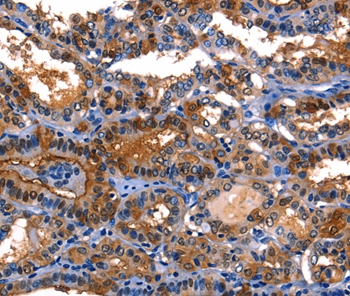

Immunohistochemical analysis of paraffin-embedded Human thyroid cancer tissue using #35748 at dilution 1/10.

应用详情:Immunohistochemistry: 1:10-1:50